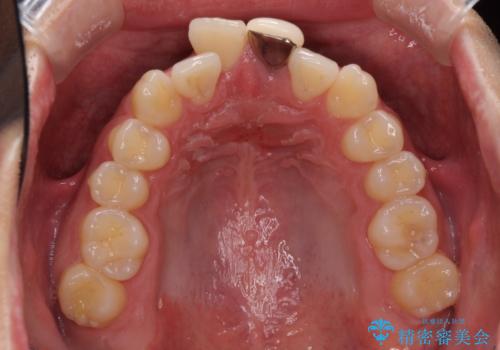

前歯の歯並びとクラウンを改善 インビザラインとオールセラミック

- 前歯の歯並びと不自然な色をした前歯のクラウンを気にして来院された患者様です。

上下前歯の歯列不正はインビザラインにより歯列を整え、その後に、前歯をオーダーメイドタイプのオールセラミッククラウンにて補綴治療することとしました。

初診時には、歯並びを整えることのみを検討されていましたが、歯列が整うにつれて不自然な色合いが気になるようになり、矯正治療を行ってから補綴治療をする計画を受け入れてくださいました。